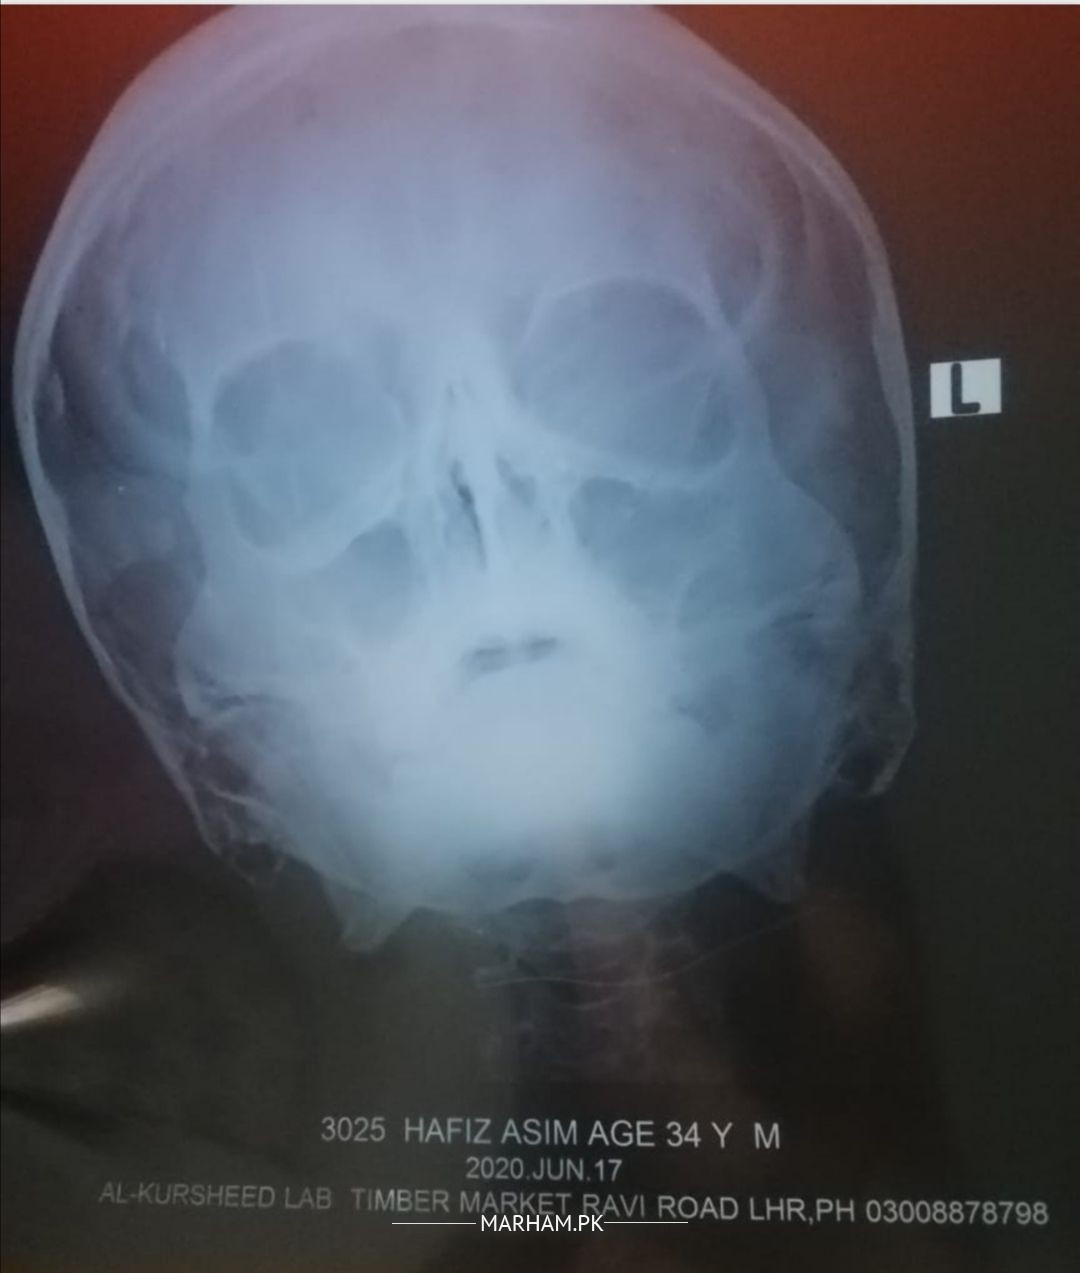

Asking For Self, Male 34, Lahore

Facing breathing difficulty periodically since some years but not continously. From the last few months, it is getting more frequent. Recent PNS x-ray is attached herewith.

Please tell me what does it show and what is the solution for it?

You have allergy and it needs immediate treatment otherwise it will progress into asthma... U can contact me through marham by online consultation for proper treatment of your disease...